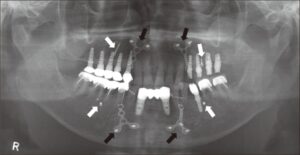

يخلط المراجعون أحياناً بين هذه البراغي وزراعة الأسنان. زراعة الأسنان هي برغي يزرع داخل العظم ليتم تركيب تاج السن عليه ومن المفترض أن يتحمل قوة المضغ ويبرز جزء منه من اللثة. أما براغي جراحة الفك أو التقويم الجراحي فهي تختبئ تماماً تحت الأنسجة الرخوة واللثة وليس لها أي اتصال ببيئة الفم.

البراغي الجراحية أصغر بكثير من زرعات الأسنان. يبلغ طولها أحياناً بضعة ميليمترات فقط. وظيفتها هي مجرد الحفاظ على قطعتي العظم بجوار بعضهما وليست تثبيت الأسنان الاصطناعية. لذلك بعد العملية لن ترى أي معدن في فمك وتكون كل هذه الوصلات مخفية تحت نسيج اللثة.